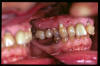

CM Caries y enfermedad periodontal avanzada

CM Caries y presencia de cálculo